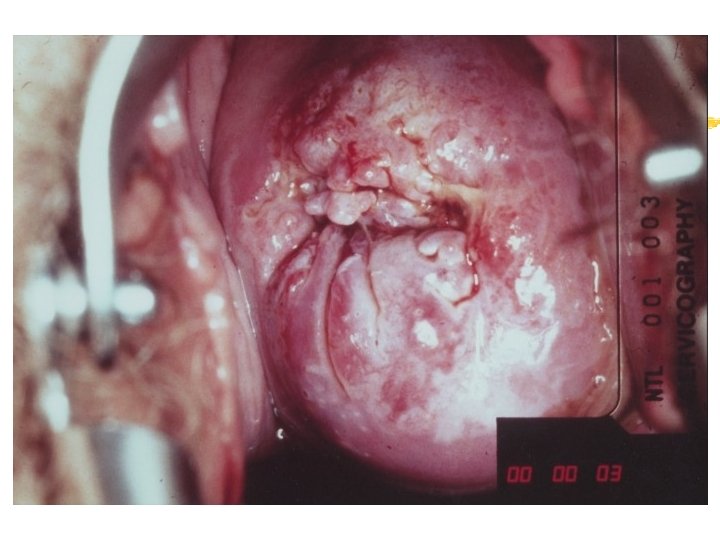

Warning signs of early cervical cancer 1. Yellowish and friable epithelium 2. Abnormal contour 3. Ulceration 4. Atypical vessels 5. Very severe colposcopic atypia 6. Large, significant lesion 7. Canal lesion, going out of range 8. Perimenopausal and post radiation

Mimics of cervical cancer 1. Severe cervicitis e. g. , herpes, syphilis 2. Benign ulceration e. g. , trauma 3. Foreign body reaction 4. Granulomatous cervical conditions 5. Granuloma inguinale 6. Lymphogranuloma venereum 7. Schistosomiasis 8. Cervical condylomata Cololposcopy aids differentiation. Histology is the gold standard

Atypical transformation zone 1. Acetowhite epithelium 2. Vascular structure a. Mosaic pattern b. Punctation c. Abnormal vessels 3. Leukoplakia

Acetowhiteness 1. SIL …dehydration of nuclear dense lesion 2. HPV …keratin swelling in HPV infected cells 3. Immature squamous metaplasia 4. Healing/regenerating epithelium 5. Congenital transformation zone 6. Inflammation 7. Adednocarcinomas Invasive squamous carcinoma

Cervicography: This is NOT Colposcopy High-quality colposcopic-type photography of the cervix Cervicoscope - Hand-held camera with a macrolens and a ring-flash Cervicogram - 35 -mm photo slide is taken Principles Recognition of lesions by means suitable magnification and illumination Fix up the problems of colposcopy 1. a less expensive form 2. noninvasive method 3. do not require expert skill

Procedures of cervicography A) Taking a 35 -mm cervicogram (1) Insert speculum and open as wide as possible … expose an entire cervix and upper vagina (2) Apply first application of 5% acetic acid by dabbing … cleanse the cervix of blood and mucus (3) View the cervix through the cervicoscope … allows time to begin taking epithelial change (4) Apply second application of acetic acid. (5) Take two cervicogram pictures B) Developing the images C) Interpreting a magnified image that was projected on the screen (1) Negative if no definitive lesions are visible (2) Atypical if there was evidence of acetowhite lesion of doubtful significance (3) Positive if there was evidence of a minor or major-grade lesion or cancer